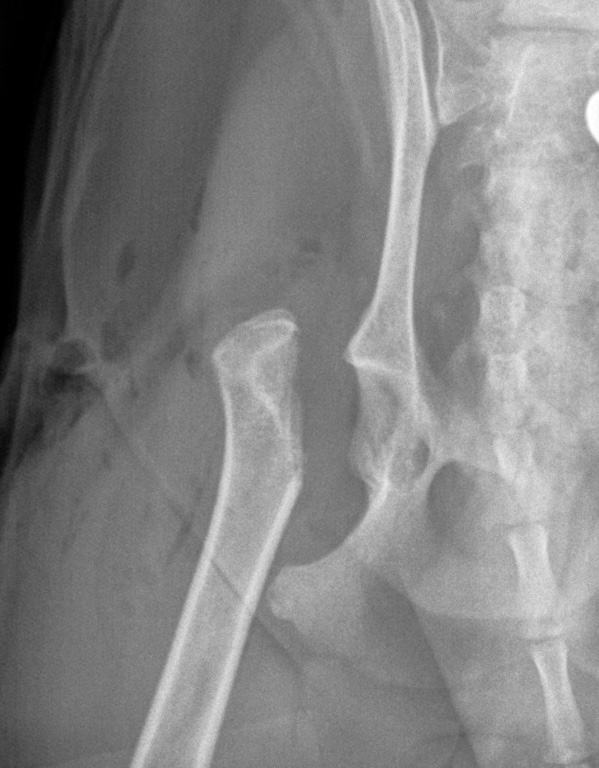

Femoral Head Ostectomy (FHO) Surgery

FHO surgery is an option for pets with severe hip pain due to conditions such as hip dysplasia, trauma, or chronic arthritis. By removing the damaged portion of the hip joint, pain can be significantly reduced, allowing many pets to regain comfortable mobility with proper rehabilitation.

Hip Dysplasia with Arthritis

Femoral Head Ostectomy (FHO) Before Surgery